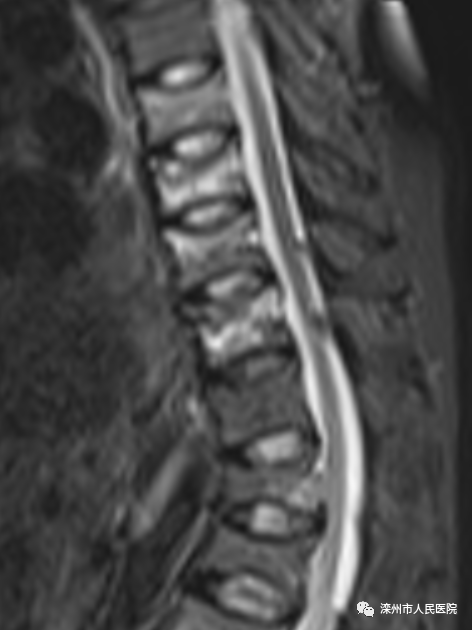

(术前核磁:白色的为新鲜骨折的椎体)

患者张某某,女性,高龄(93岁),同样严重骨质疏松,无明显诱因下出现胸背部疼痛,腰椎核磁示胸12椎体压缩骨折。